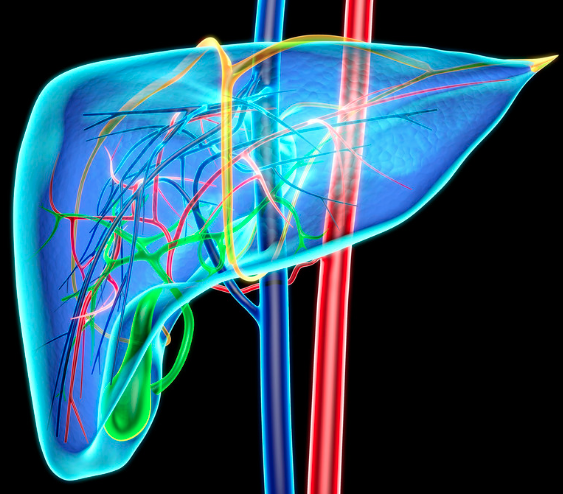

(Bild: Canva Design/Hank Grebe; Getty Images)